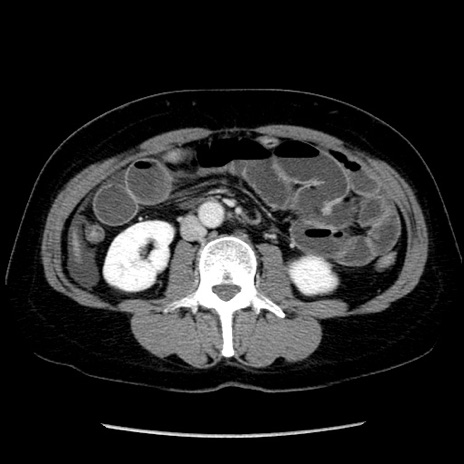

症例6(横断像)

【症例】50歳代女性

【主訴】下腹部痛

【現病歴】本日朝より下痢2回あり。 昼食を食べた後、嘔吐3回、下腹部痛認め、症状軽快せず、当院救急搬送。

【既往歴】卵巣癌術後(8年前に当院で卵巣摘出)

【身体所見】 意識清明、腹部:平坦、腸蠕動音→、やや硬、下腹部自発痛・圧痛あり、反跳痛あり、筋性防御なし。

【データ】WBC 16000、CRP 0.01